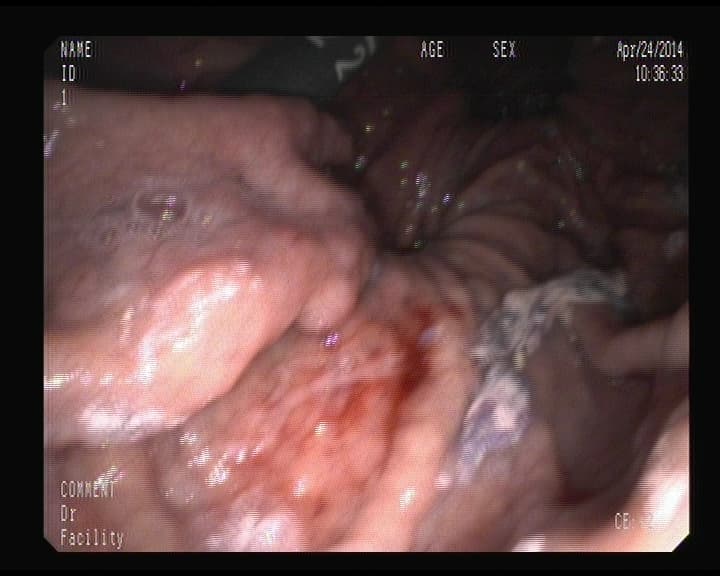

Punto sangrante anterior foto, ya solucionado.

Resultado del punto sangrante en duodeno ya tratado.

Hemorragia digestiva alta.

Punto sangrante en Duodeno, solucionado con colocación de un clips metálico,